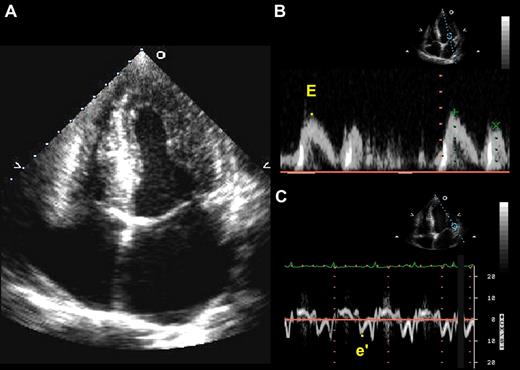

Representative echocardiographic images from a patient with sickle cell disease. (A) Apical 4-chamber view showing concentric left ventricular hypertrophy and a dilated left atrium. (B) Doppler of the mitral inflow used to obtain a peak E velocity for early ventricular filling. (C) Tissue Doppler of the lateral mitral annulus used to obtain a peak e′ velocity. The E/e′ ratio is an indicator of left ventricular filling pressures and is used in the assessment of diastolic dysfunction.